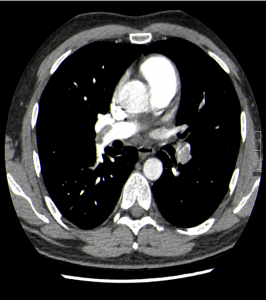

Nuestro paciente tiene síntomas respiratorios y un valor elevado de Dímero D. El Angio-TC nos permite hacer una valoración más detallada del estado de la anatomía vascular pulmonar así como del del corazón: También nos va a proporcionar una visión más en detalle del parénquima pulmonar.